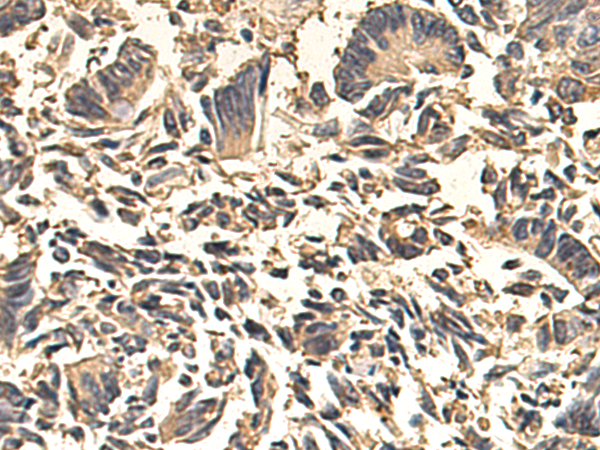

IHC positive control:

human lymphoma tissue and human tonsil tissue

IHC Recommend dilution:

30-150